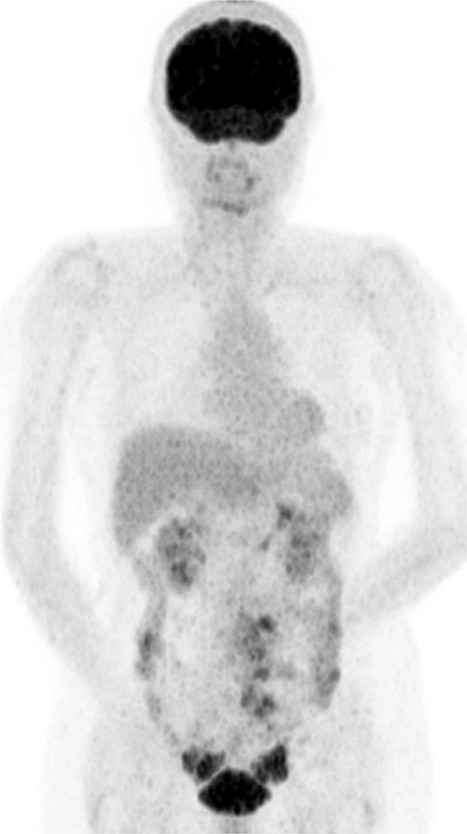

During her first visit, transvaginal ultrasonography revealed solid masses in both ovaries. Blood tests revealed unremarkable findings. Pelvic magnetic resonance imaging (MRI) revealed a mass measuring 2.3 cm in the right ovary and another one measuring 5 cm in the left ovary, both with a slightly high signal intensity on T2-weighted images and isointense with the myometrium on T1-weighted images, with smooth surfaces and homogeneous internal structures. There was also restricted diffusion, mild contrast enhancement, right external iliac lymph node enlargement, and disseminated mesenteric nodules (Fig. 1). CT revealed bilateral solid ovarian masses with mild contrast enhancement. The presence of multiple masses in the right pelvic cavity and mesentery suggested peritoneal dissemination. Positron emission tomography (PET-CT) revealed uptake in the ovaries and mesentery (Fig. 2). Upper and lower gastrointestinal endoscopy revealed unremarkable findings. Considerably, ovarian cancer with multiple metastases was suspected.

Positron emission tomography (PET-CT) scan showing FDG uptake in the ovaries and mesentery.